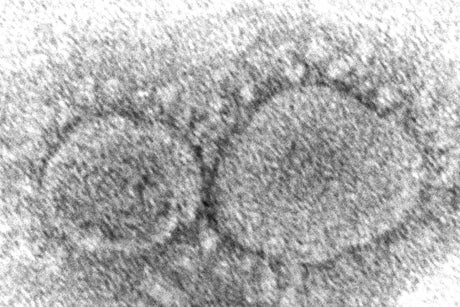

Evidence is mounting that having COVID-19 may not protect against getting infected again with some of the new variants. People also can get second infections with earlier versions of the coronavirus if they mounted a weak defense the first time, new research suggests.

How long immunity lasts from natural infection is one of the big questions in the pandemic. Scientists still think reinfections are fairly rare and usually less serious than initial ones, but recent developments around the world have raised concerns.